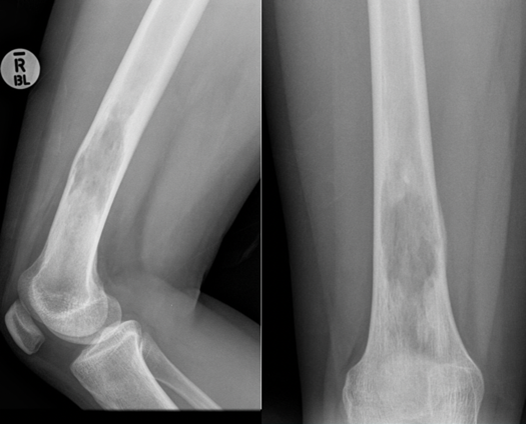

Osteosarcoma. There are many types of osteosarcoma but the most common is the classic intramedullary type which usually originates from the intramedullary cavity of the metaphyseal area of long bones. It is the most common type of bone sarcoma overall. It is most often found in teenagers and young adults. Any pathological fracture in a young person must be considered malignant until proven otherwise. The treatment of an osteosarcoma is classically neoadjuvant chemotherapy – surgery – adjuvant chemotherapy. The biopsy to diagnose bone sarcomas should be done by a sarcoma specialist to prevent difficulties with future surgery and spread of the tumour locally. The 5-year survival for patients with osteosarcoma is between 60% and 70%.

Endoprosthetic replacement. An example of a wide local resection of a patient who had an osteosarcoma of her proximal tibia. The initial X-rays show the pervasive lytic lesion of the proximal tibial diaphysis and metaphysis. The subsequent X-rays show an endoprosthetic replacement called a proximal tibial replacement. The knee has been replaced with a hinge-type knee replacement and the bone and tumour of the proximal tibia has been replaced by a modular metal prosthesis with a stem cemented into the distal femur and the proximal tibia.